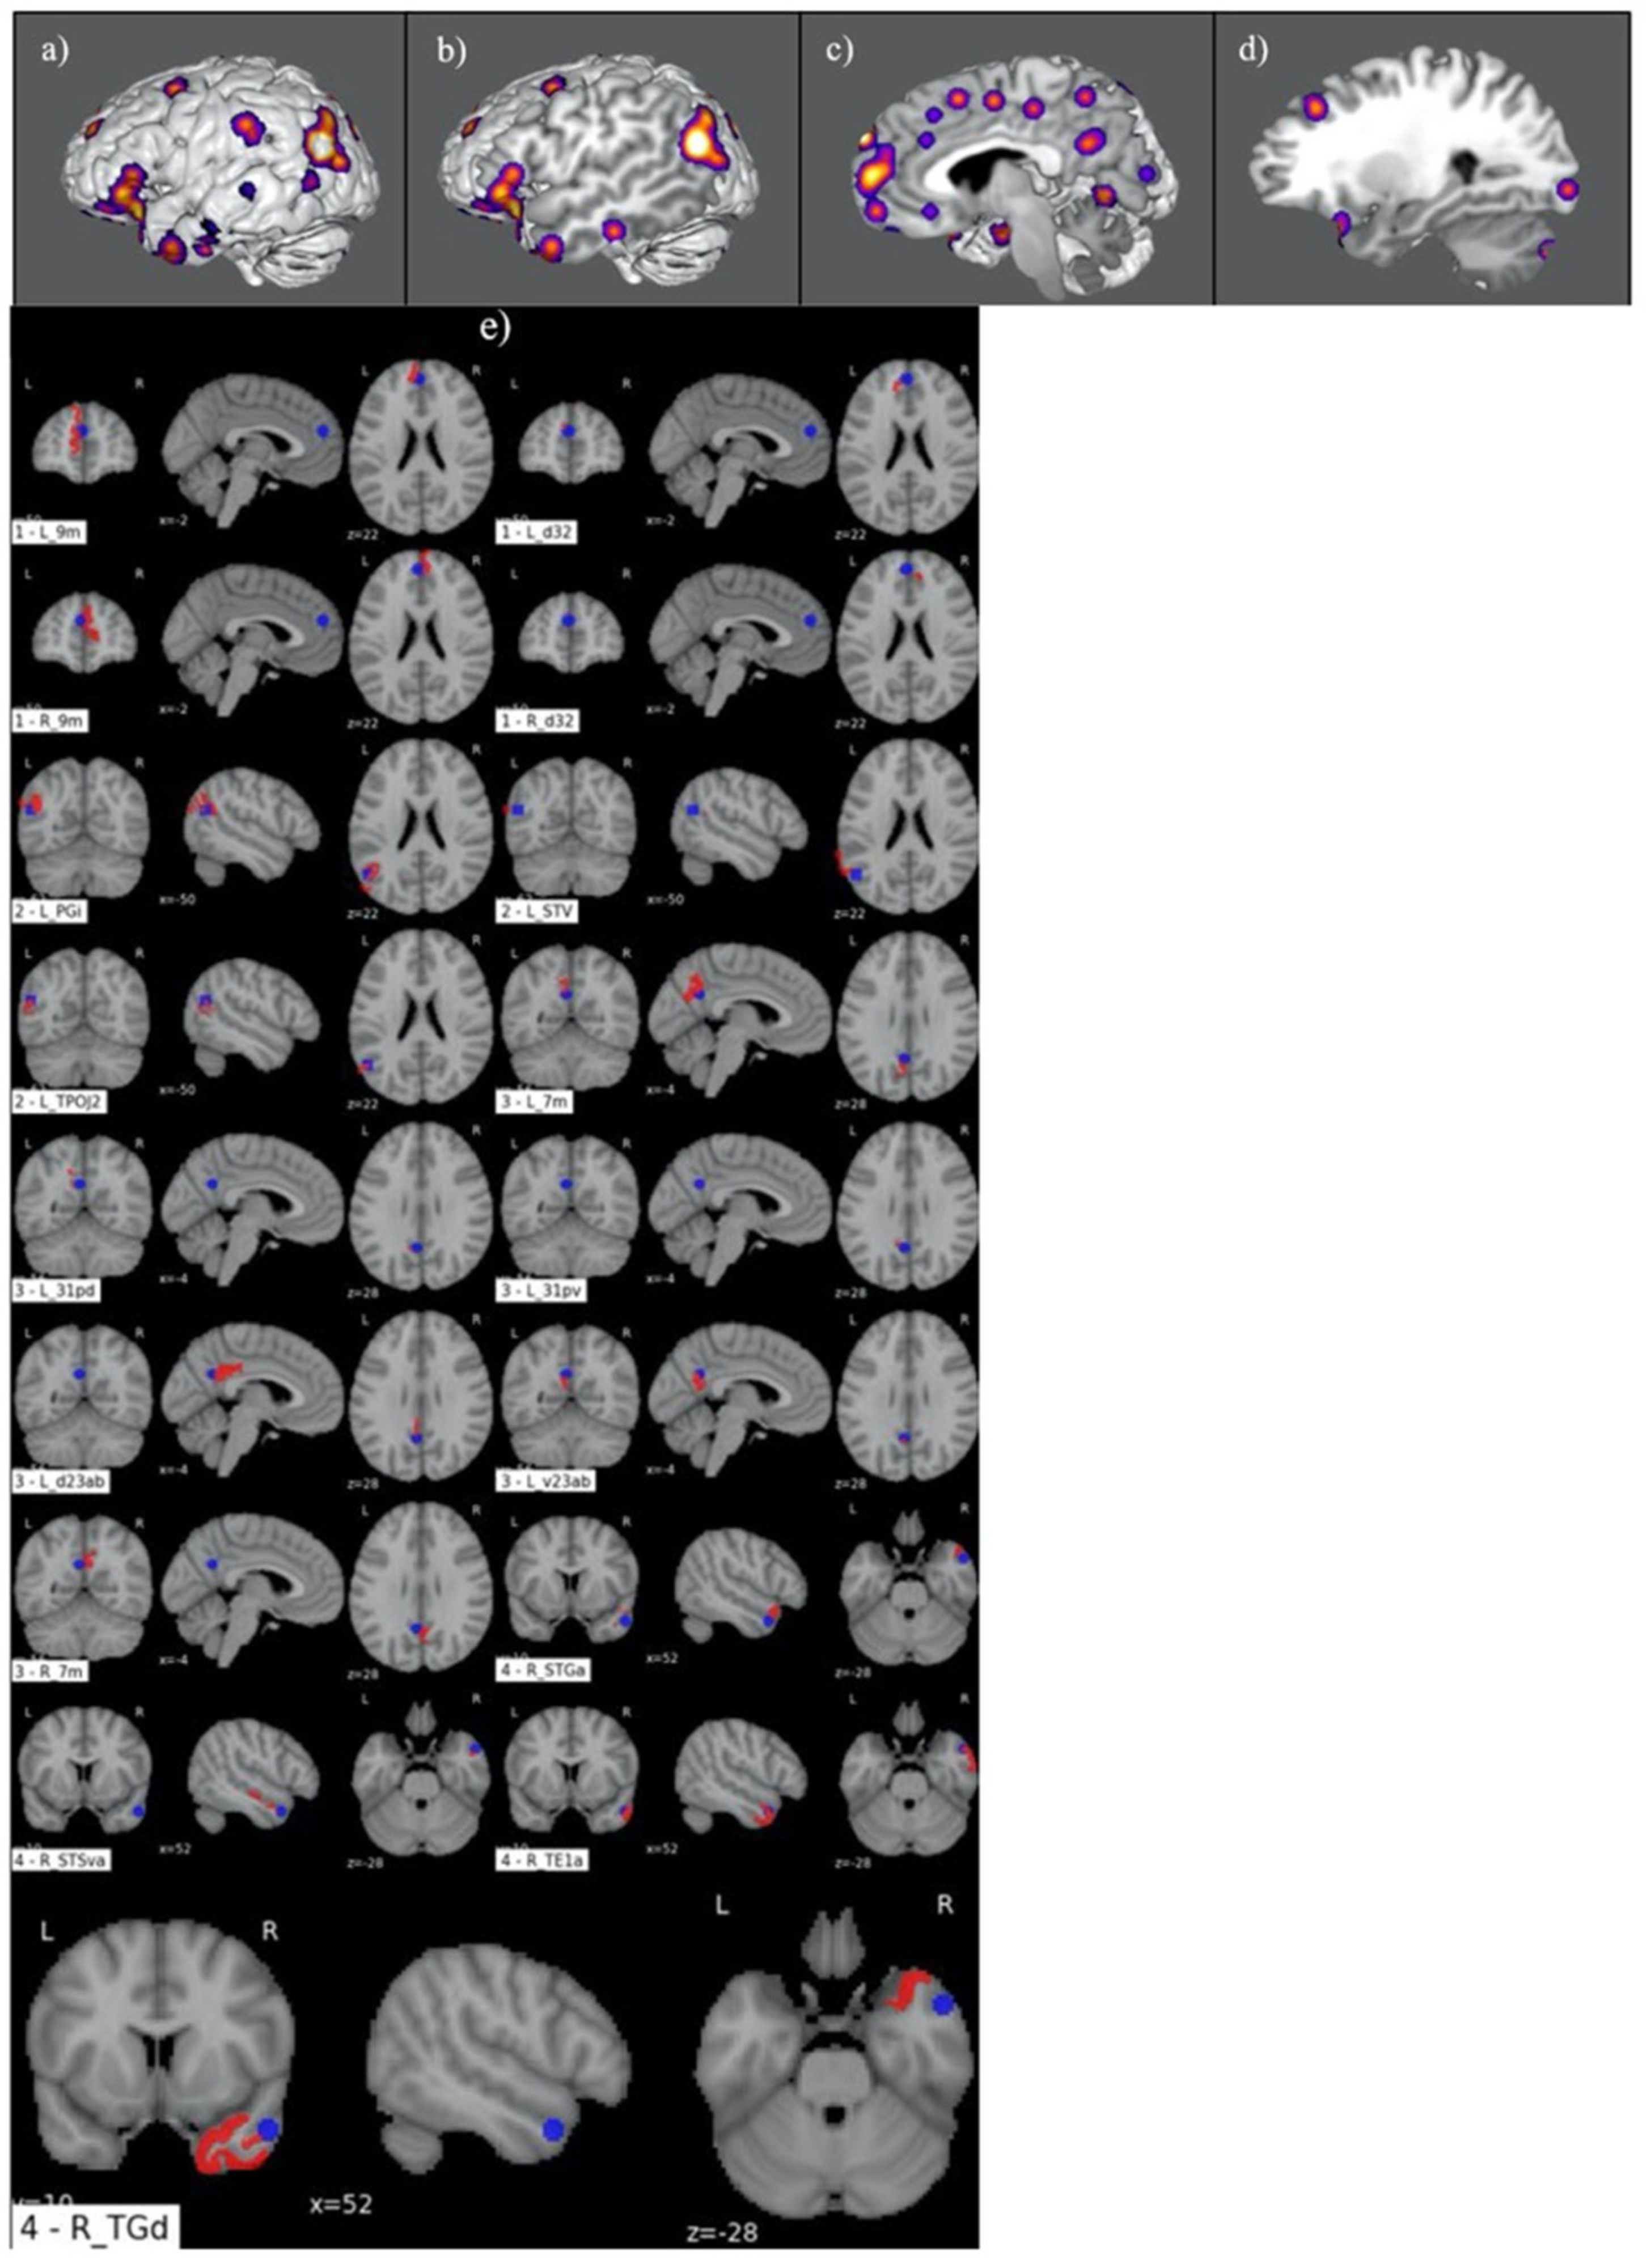

3.1. Judgement Activation Maps

3.2. Parcellation-Based Comparative Analysis